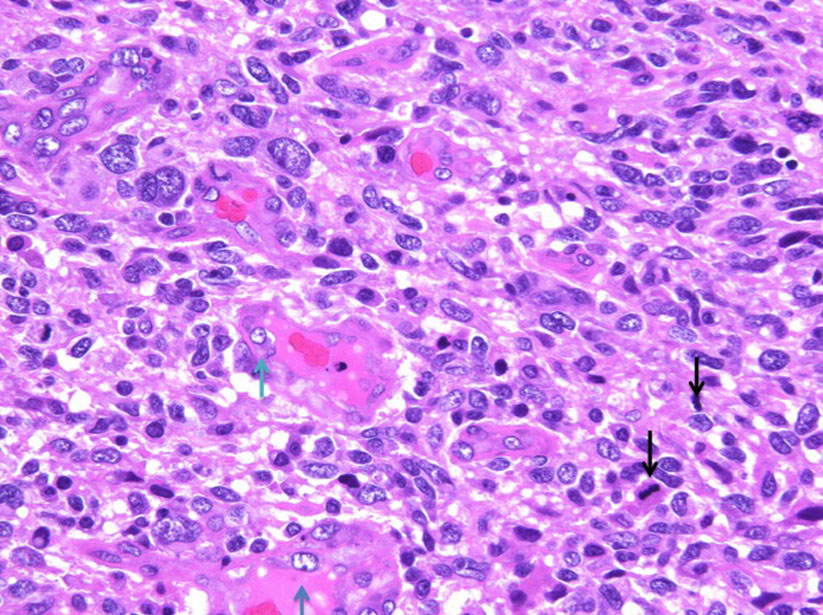

腫瘍細胞核の多態性と血管内皮細胞核の腫大(青↑)および核分裂像(黒↓)が認められる。

HE x400